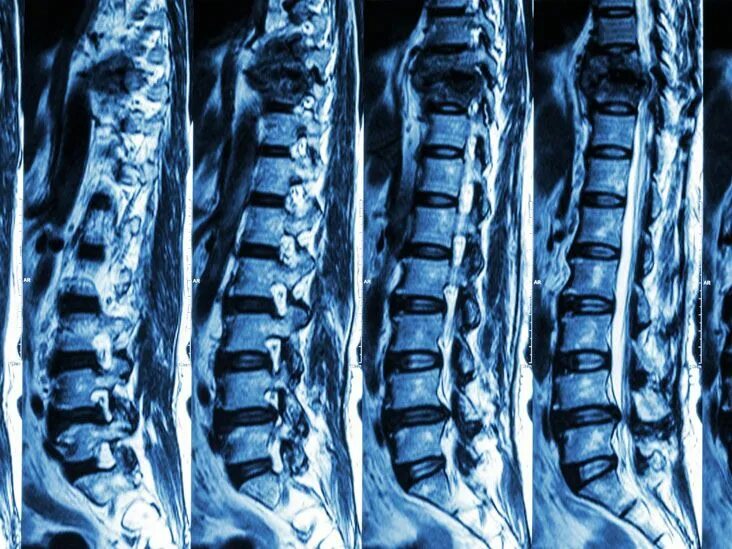

Чем отличается кт от мрт поясничного отдела